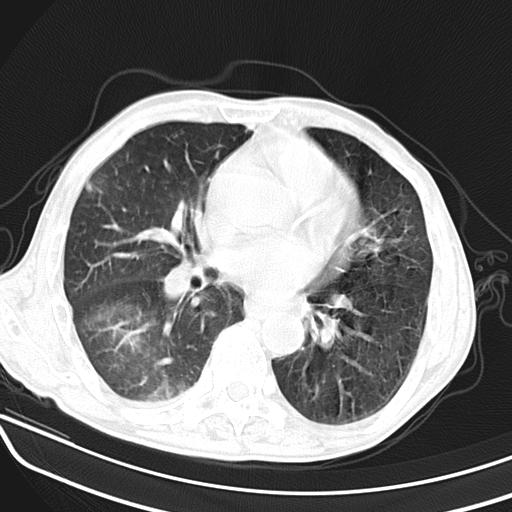

抗炎治疗10天后复查

抗炎治疗10天后复查:右上肺模糊阴影明显减少。